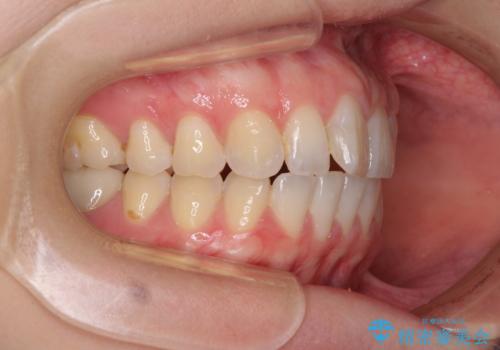

気になる上の歯を改善 インビザライン矯正

- 矯正治療の後戻りが気になるとのことで来院された患者様です。

上顎の後戻りをインビザライン・ライトで治療することとしました。

上顎のみの治療を希望されたため、咬み合わせをしっかりと改善することはできませんでしたが、審美面が大きく改善され、日常生活の機能面でも不具合を感じることはなく、大変満足していただきました。